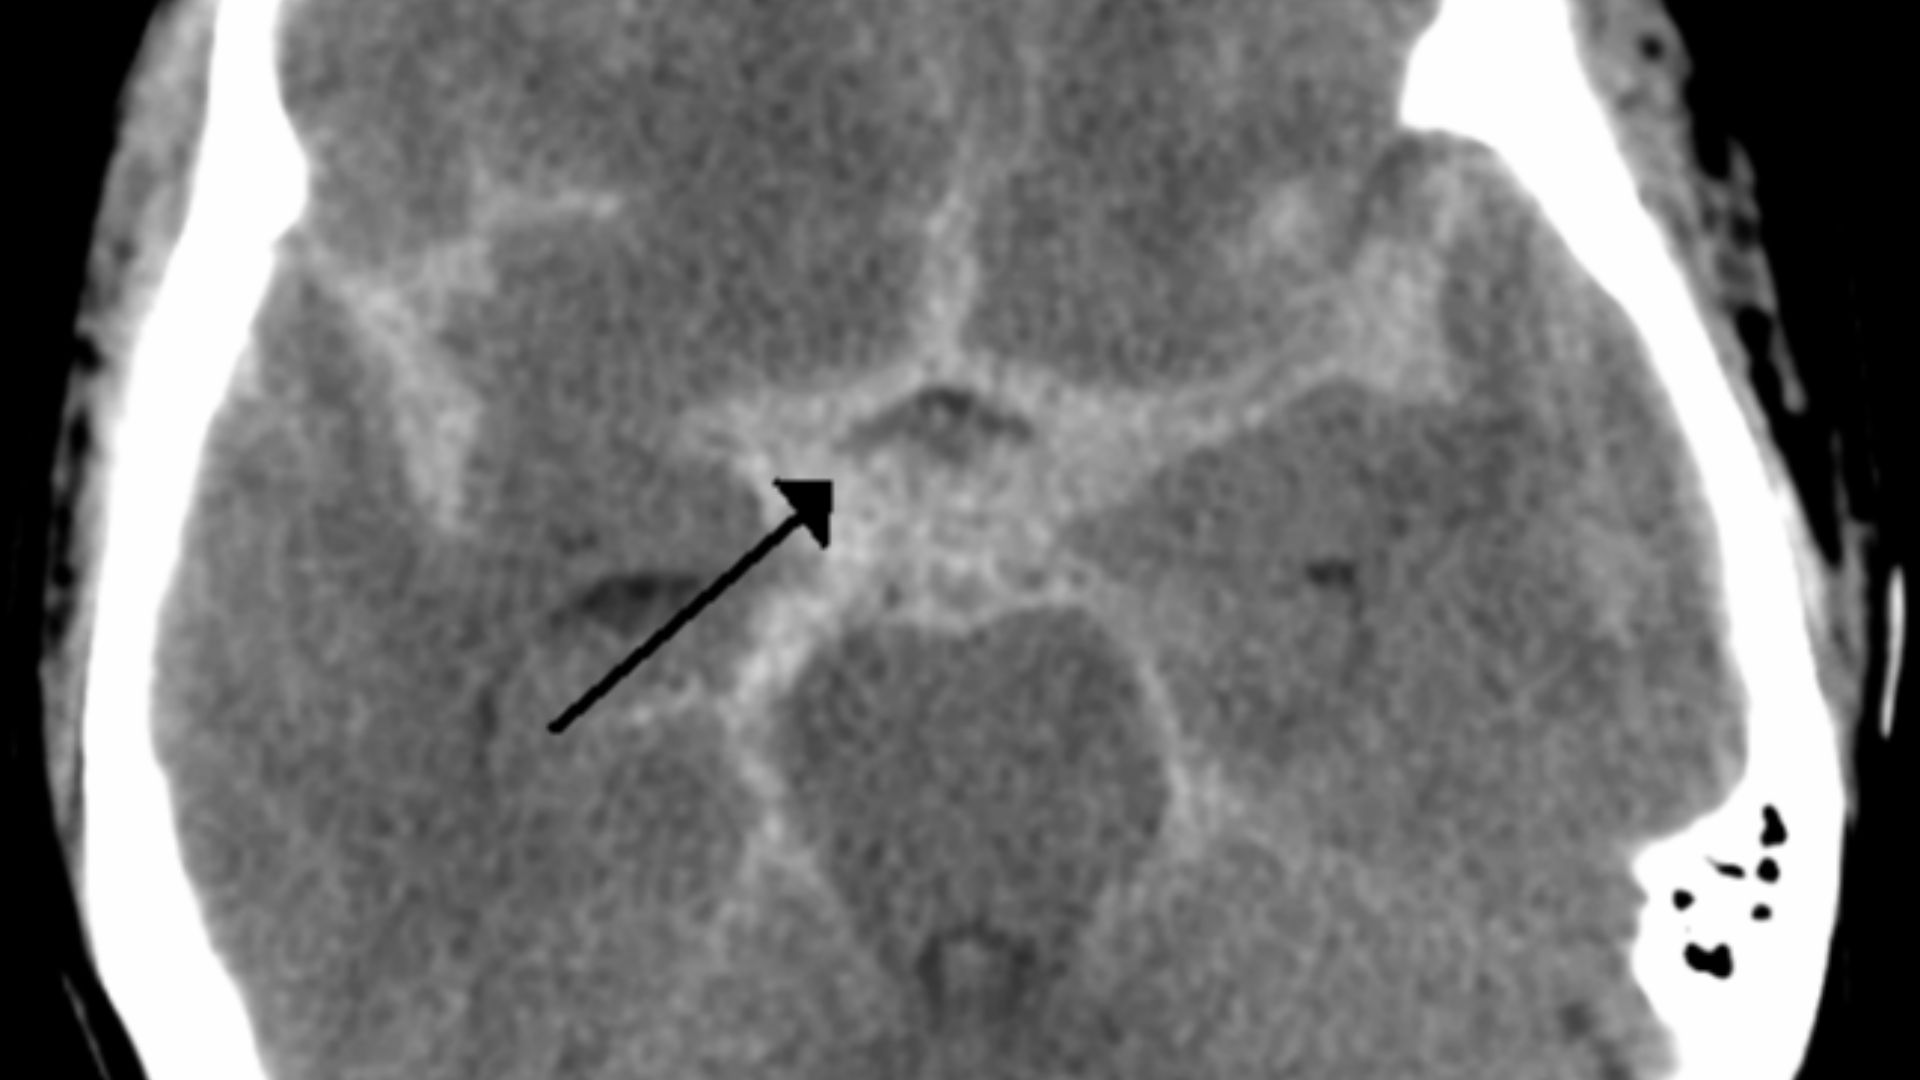

A Life-Threatening Diagnosis

Clarke had suffered a subarachnoid hemorrhage—a type of stroke caused by a brain aneurysm. It’s a condition that can be fatal without immediate treatment. Within a matter of hours, her life had shifted from rising star to fighting to survive.

Emergency Brain Surgery

She underwent urgent brain surgery in 2011 to save her life. The procedure was invasive and dangerous, but necessary. At just 24 years old, Clarke now found herself facing a situation most people never imagine and unsure if she would fully recover.

A Complication That Made Things Worse

After surgery, Clarke developed aphasia, which affected her ability to speak and process language. At one point, she couldn’t even remember her own name. She later revealed that parts of her brain had been permanently damaged by the bleed. Something she would carry with her long after the physical recovery.